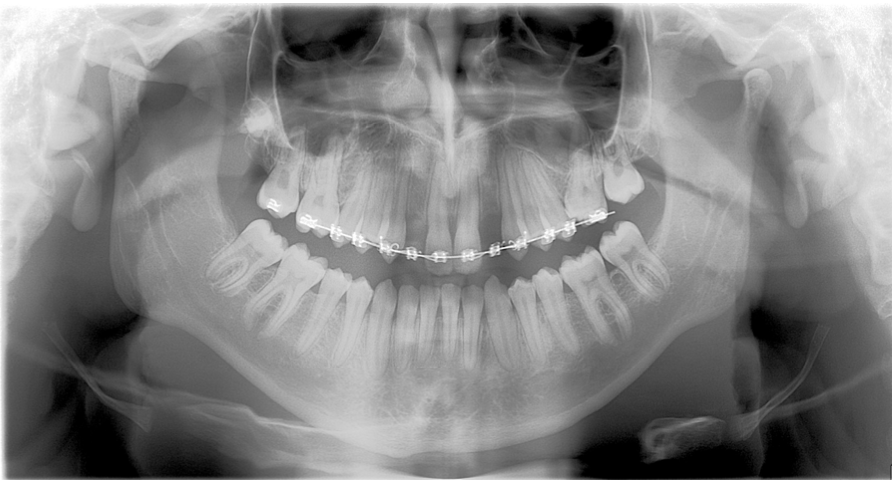

DPT- show full mandible and maxilla, roots, crowns can give good assessment of dentition

useful for patients with a large lesion in the bone as it can show a large area at once